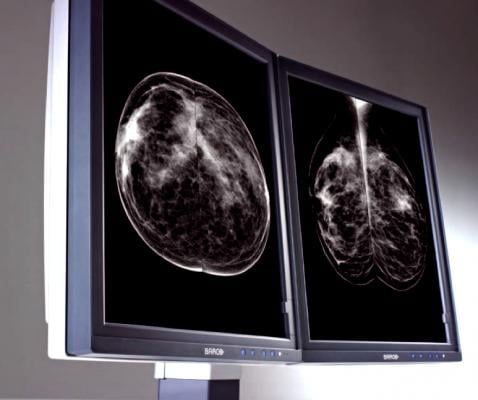

April 26, 2016 — A new study from Elizabeth A. Rafferty, M.D., formerly of Massachusetts General Hospital, and colleagues evaluated the screening performance of digital mammography combined with tomosynthesis compared with digital mammography alone for women with varying levels of breast density. The study appears in the April 26 issue of JAMA.

Breast density is associated with reduced mammographic sensitivity and specificity, and increased tumor size and worsened prognosis are associated with increased breast density. Currently, 24 states have laws mandating that women be notified of the implications of breast density, thereby encouraging discussions between patients and physicians regarding the need for supplemental screening. However, which, if any, additional testing should be recommended for women with dense breasts is not known.

This study included data from screening performance metrics from 13 U.S. institutions, which were reported for 12 months using digital mammography alone and from the date of introduction of tomosynthesis. Subgroups included the four breast density categories used for clinical reporting. Overall and invasive cancer detection rates and recall rate with and without tomosynthesis were analyzed in patients with both nondense and dense breasts.

Of 452,320 examinations, 278,906 were digital mammography alone and 173,414 digital mammography plus tomosynthesis; 2,157 cancers were diagnosed. The researchers found that the addition of tomosynthesis to digital mammography for screening was associated with a 50 percent increase in cancer detection rate and a 14 percent reduction in recall rate for women with both dense and nondense breast tissue.

“These combined gains were largest for women with heterogeneously dense breasts, potentially addressing limitations in cancer detection seen with digital mammography alone in this group, but were not significant in women with extremely dense breasts,” the authors reported.

They also noted that for women classified as having dense breast tissue, most have heterogeneously dense breasts, mandating caution in drawing conclusions regarding the performance of tomosynthesis for the small proportion of women with extremely dense breasts.